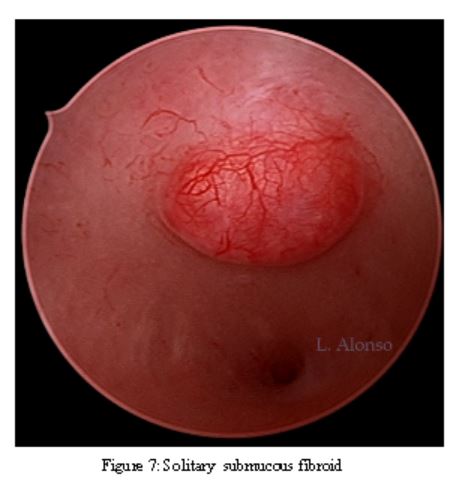

Hysteroscopy is essential in the evaluation of AUB and especially in the office environment where it is cost effective and well tolerated by patients. Dr. Linda Bradley, a preeminent leader in hysteroscopic surgical education has coined the phrase, “My hysteroscope is my stethoscope.” As gynecologists, we should be as adept at using a hysteroscope in the office as the cardiologist is at using a stethoscope. Hysteroscopy remains the gold standard for evaluation of the uterine cavity as it improves our diagnostic capabilities over blinded procedures such as endometrial biopsy and dilation and curettage and has consistently shown superiority over 2D and 3D sonography modalities for identification of intracavitary lesions. Figure 5, 6, 7